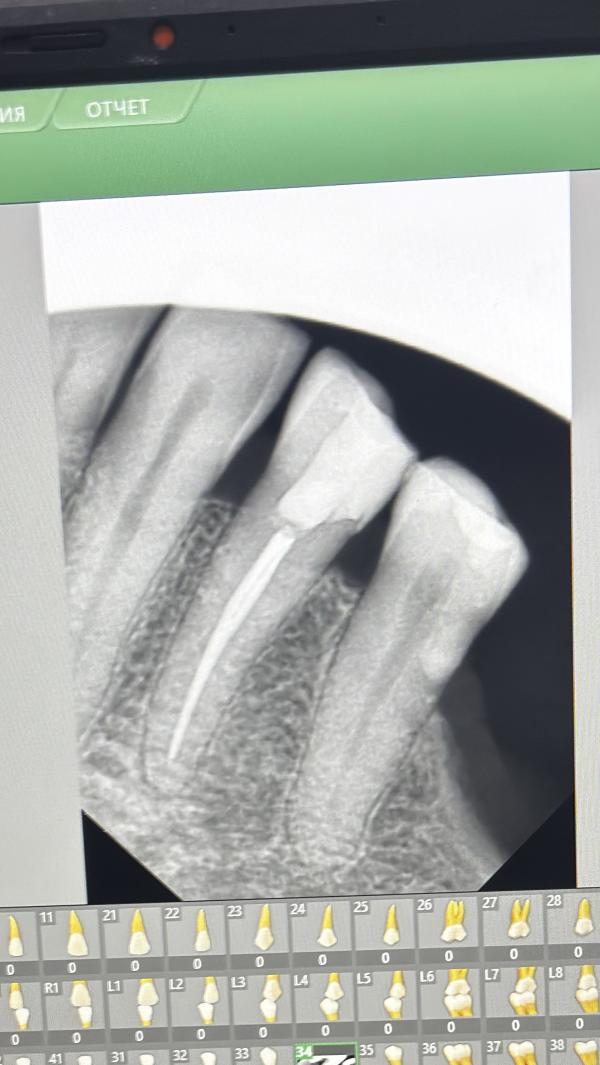

Возрастная пациентка

Лечение кариеса/ пульпита